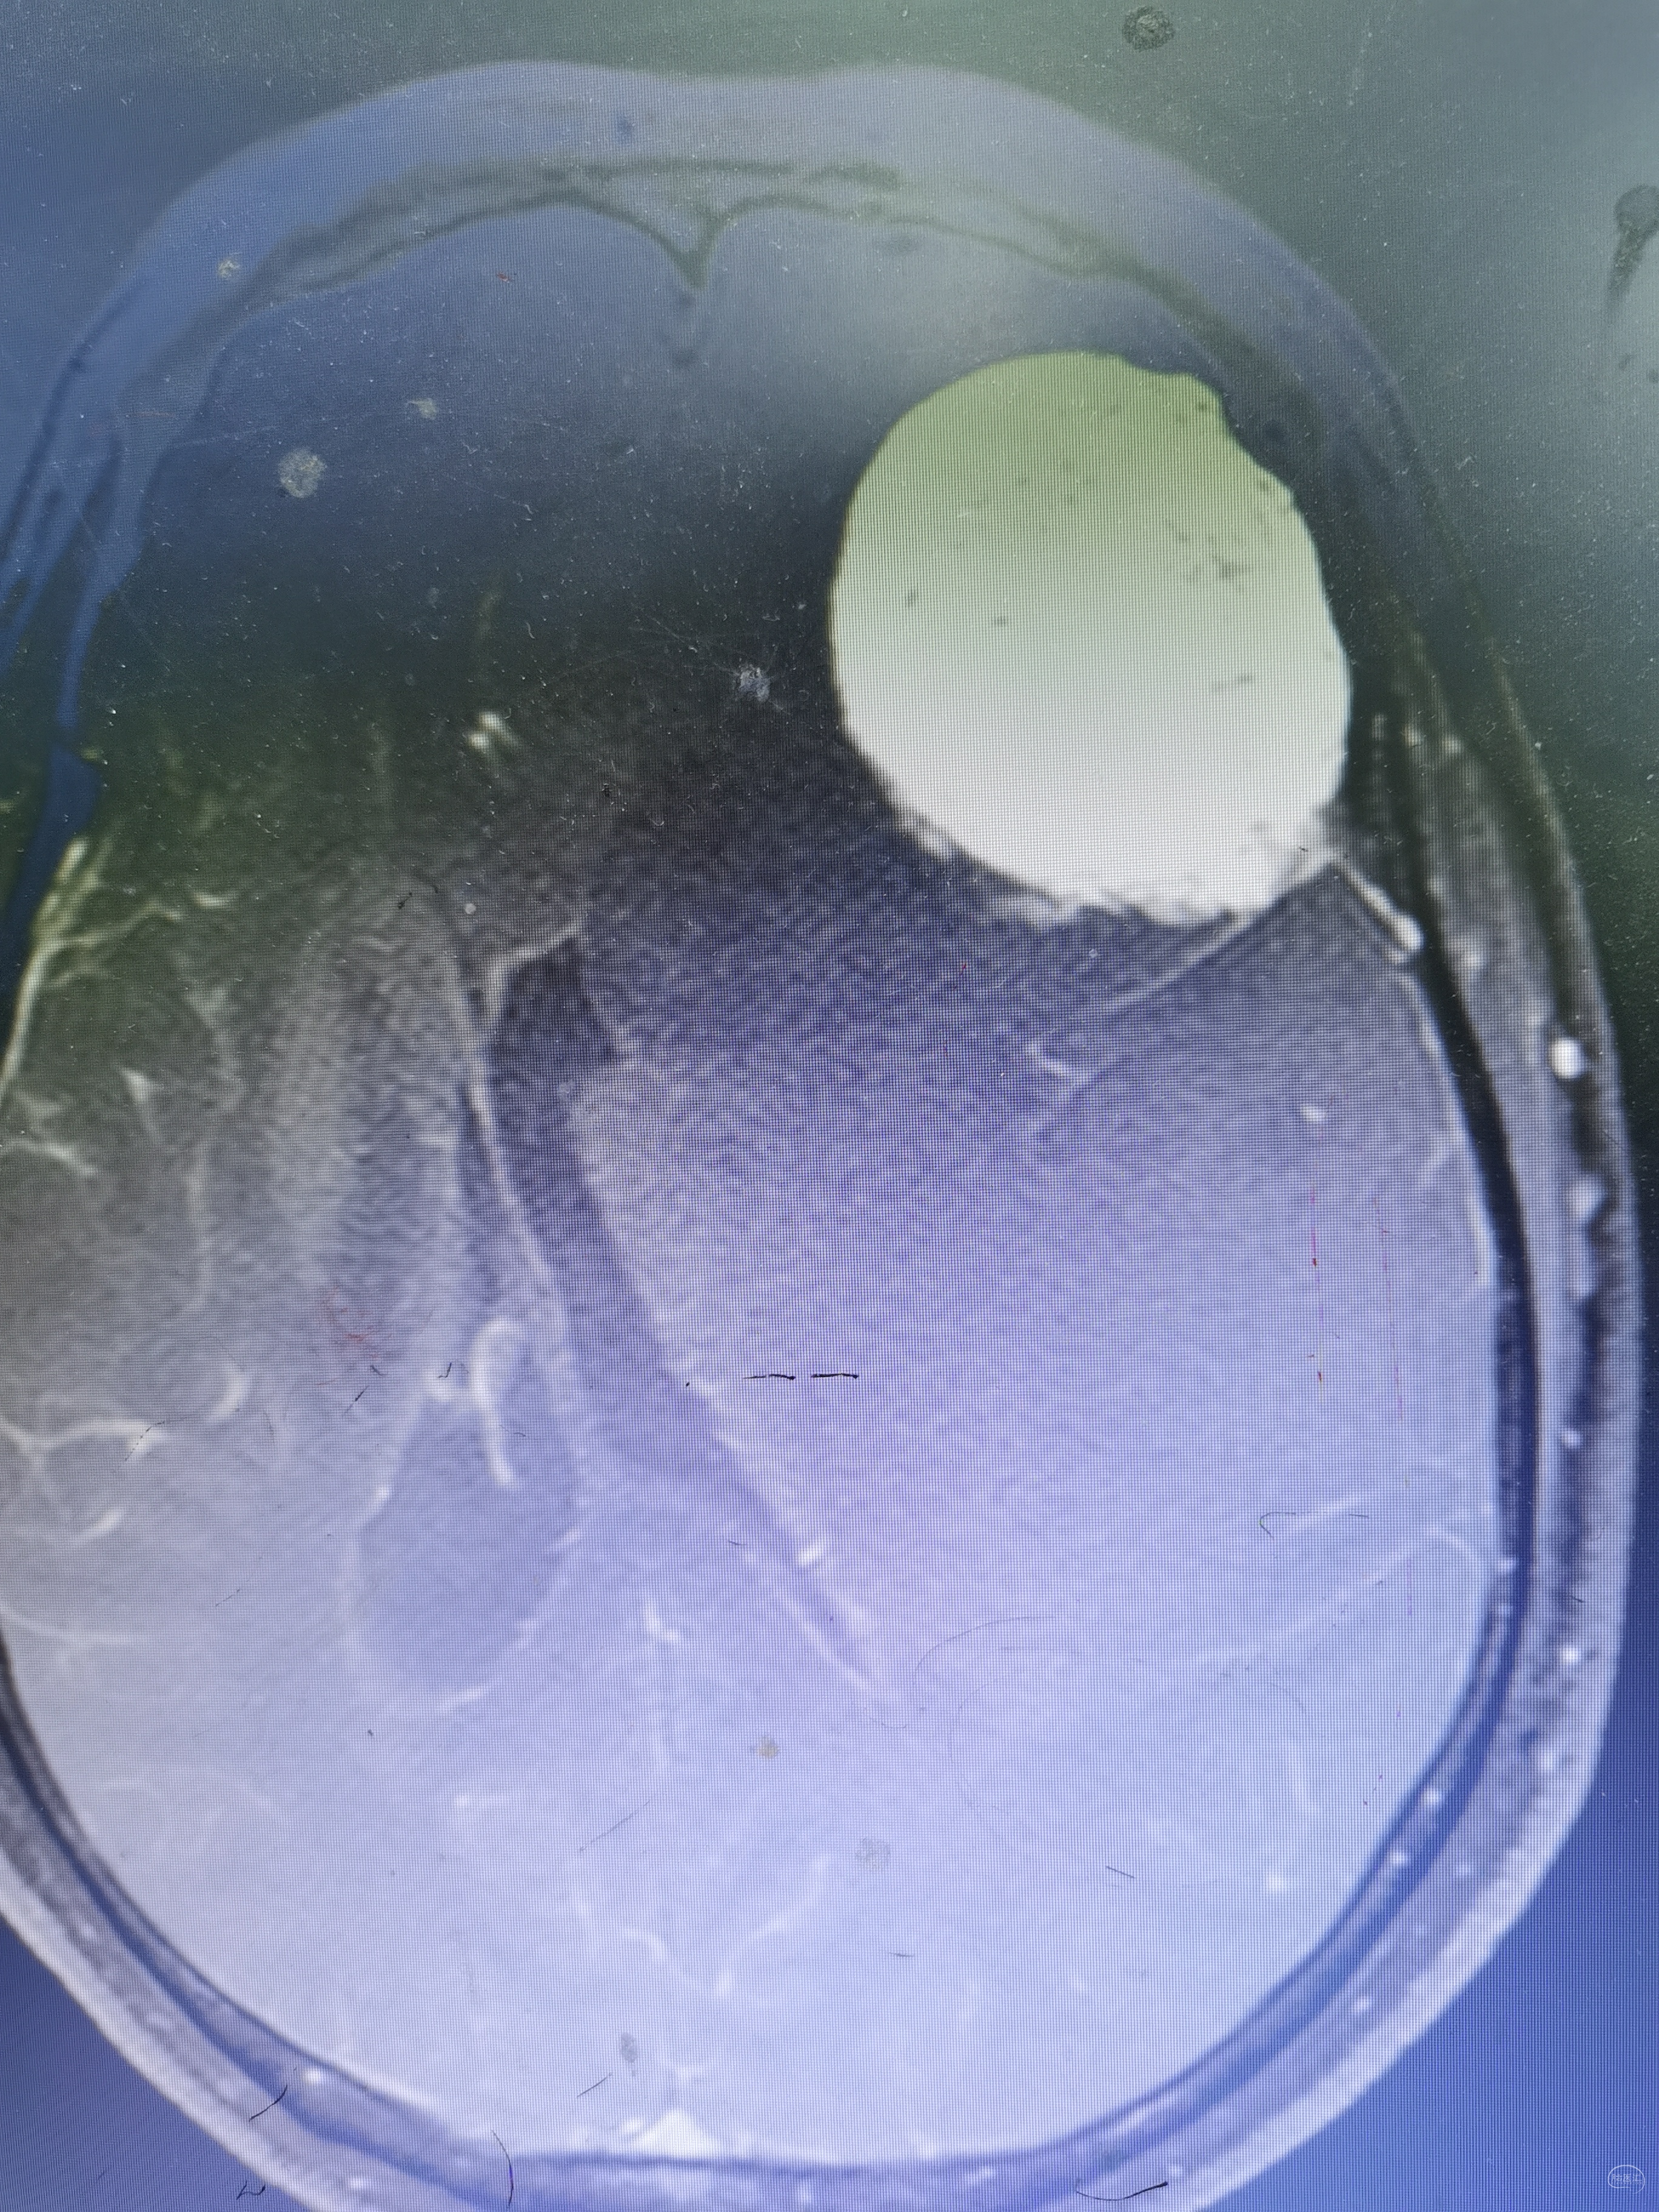

术前头颅MRI检查提示为左侧额叶占位性病变,增强强化均匀,似有脑膜征。考虑为脑膜瘤,蝶骨棘外侧型。

术后头颅MRI检查切除满意